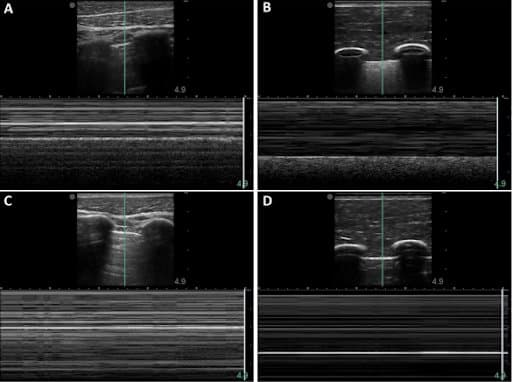

When the M-mode line was centered in the pleural lining, the baseline porcine subject provided the typical “sea-shore” sign (A). The post-injury porcine M-mode image lost this appearance and instead presented a “stratosphere sign”, indicating a lack of lung sliding (C). The synthetic phantom produced similar “sandy beach” characteristics (B) when motion was functional on the apparatus, and it produced the “barcode” when motion was halted (D).

Results: “When compared to PTX images acquired in swine, images from the phantom were similar in both PTX negative and positive mimicking scenarios.”